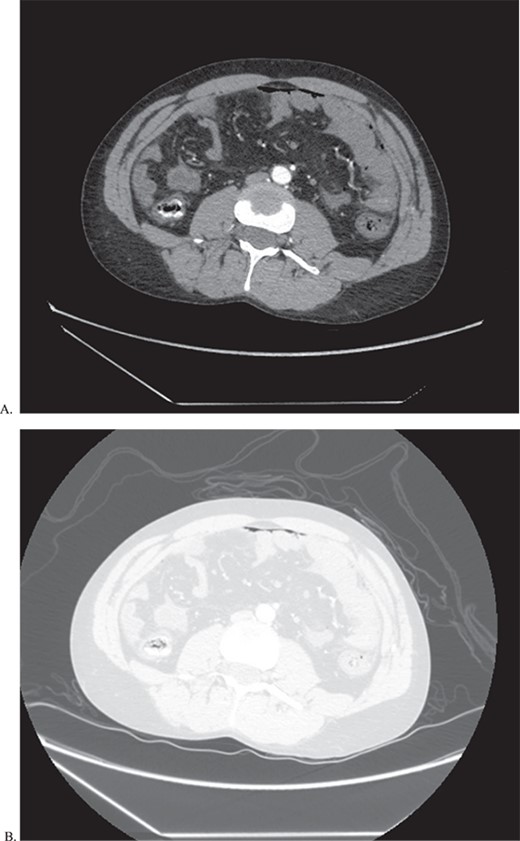

A 21-year-old male presents to the emergency department (ED) with acute onset abdominal pain. The patient has a clinical history suggestive of EDS including aortic insufficiency, joint instability, spontaneous pneumothorax, acquired foot deformity, and iliofemoral deep vein thrombosis and has been undergoing work up for EDS. Initial CT of the abdomen and pelvis (Fig. 1) revealed pneumoperitoneum and free fluid suggestive of a perforated hollow viscus without any visceral aneurysms. Therefore, the patient was taken to the operating room (OR) emergently.

CT of abdomen and pelvis in both abdominal (A) and lung (B) window to show pneumoperitoenum as well a thickened loops of bowel.